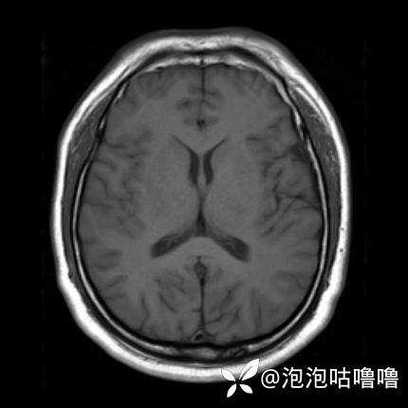

- CT不是万能的! 对于超早期的脑梗,MRI(磁共振)特别是DWI序列(弥散加权成像)比CT敏感得多,能更早地发现病灶。